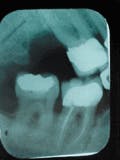

In early 1988, a tri-calcium phosphate bone graft was done on #30 at the mesial and in the furcation. The radiograph shows excess graft material at the margin that was later reduced to a more acceptable height. The patient returned to our office with no sign of disease and a 3 mm pocket at #30 mesial.

1988